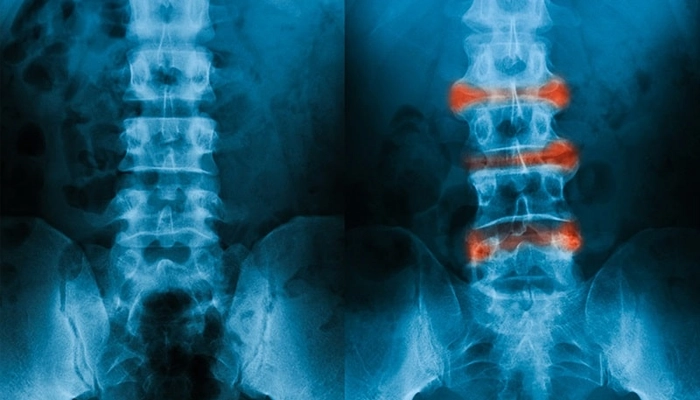

X-quang khớp cùng chậu: phát hiện xơ cứng, dính khớp.

Hình ảnh chụp Xquang của người bình thường so với người bị viêm cột sống dính khớp